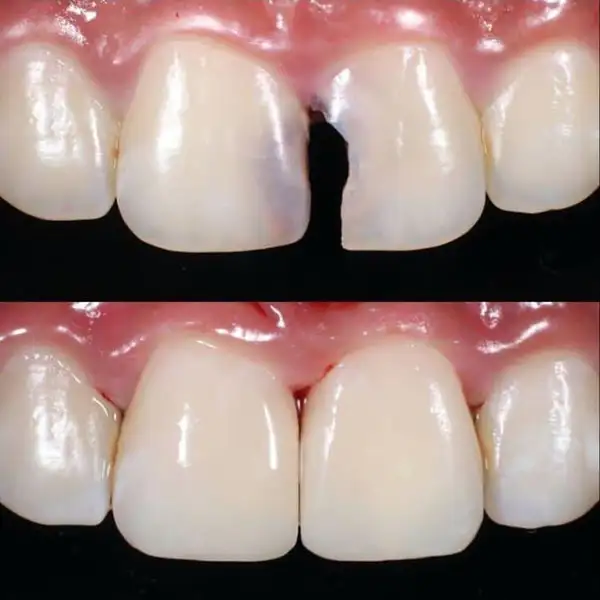

Enhances the appearance of your smile using:

- Smile designing

- Veneers

- Tooth reshaping

- Gap correction

Improves tooth shape, color, alignment, and overall smile harmony. Perfect for confidence and aesthetics.